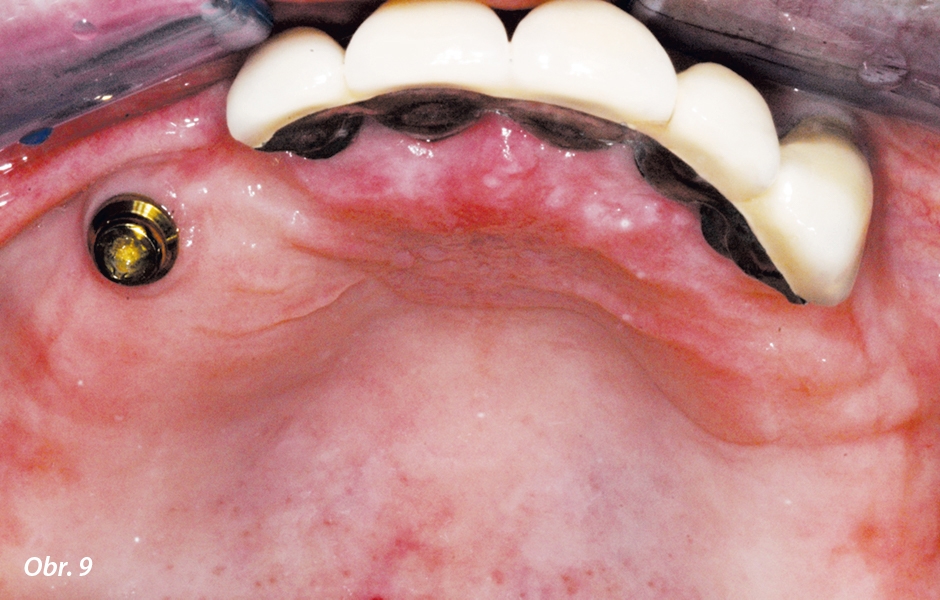

Zahrnuje zlepšení retence, stability a estetiky. Příklad opory je vidět na obr. 8. Kombinovaný příklad podpory v ukotvení a estetice je vidět na obr. 9: jeden implantát v oblasti horního pravého špičáku poskytuje pacientově ČSN skrytou, ale strategickou výhodu.

Jeden strategicky umístěný implantát v oblasti horního levého špičáku poskytuje lepší ukotvení pacientovy ČSN. Estetika náhrady není narušena, protože se kotevní prvek skryje pod sedlo náhrady.

Strategicky umístěný implantát nahrazující pravý horní špičák opatřený attachmentem